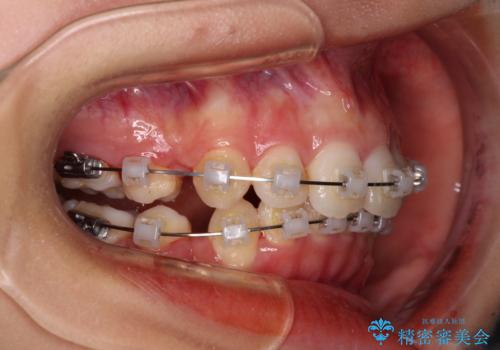

- 矯正装置

- クリアブラケット

補助装置を用いて奥歯の咬み合わせを改善しながら歯列を後方に移動させ、上下左右第一小臼歯を4本抜歯することで八重歯や口元の突出感を改善することとしました。

奥歯の咬み合わせの不正が顕著であったため、表側のワイヤー装置を選択して矯正治療を行うこととしました。

補助装置を併用したおかげでスムーズに奥歯の咬み合わせを改善することができ、我々も予想できないくらい理想的な仕上がりにすることができました。